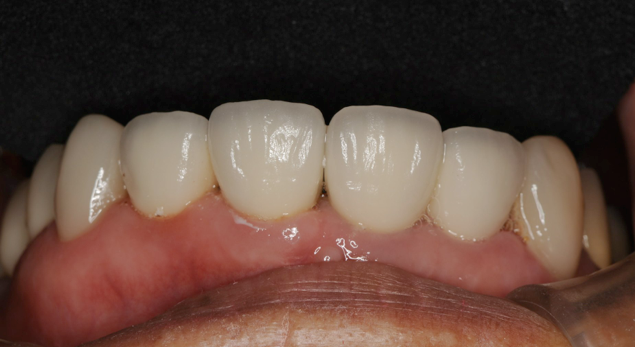

なんとか綺麗な歯が入りました。最初に歯が折れた時も差し歯はグラスファイバーの土台をいれていたので、根っ子が折れずに使えたと思います。これが保険の銀合金の硬い土台だったなら根っ子ごと折れて抜歯になっていたでしょう。